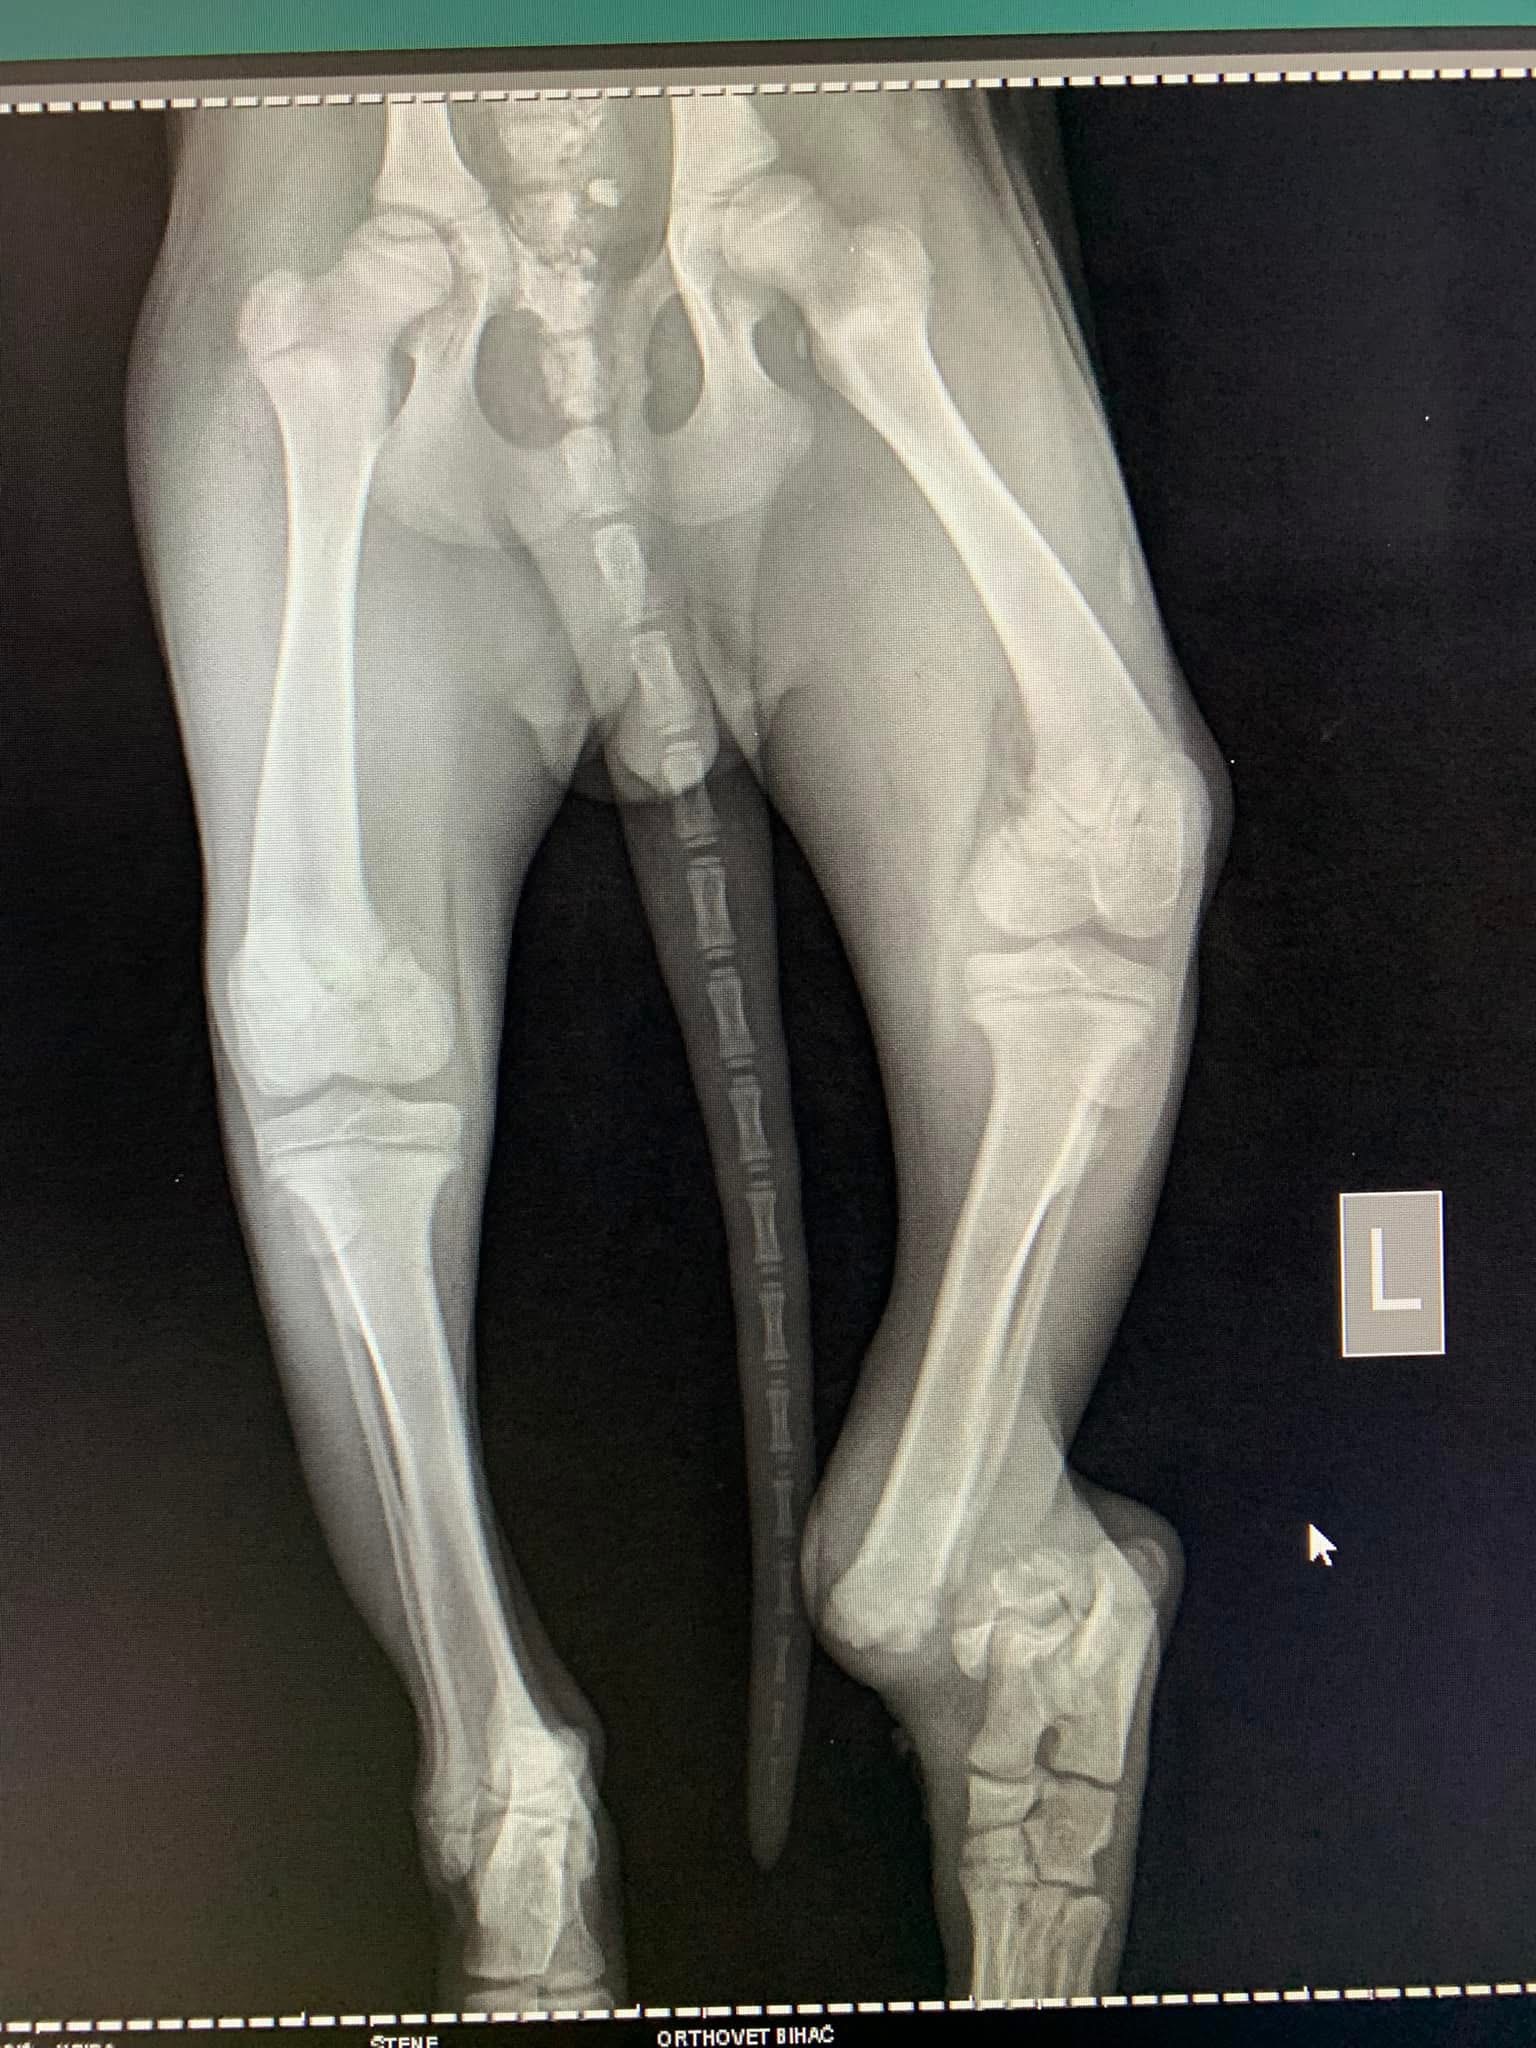

- Liječenje prijeloma kostiju, uključujući intraartikularne frakture

- Liječenje luksacije patele(Luxatio Patellae) Trohleoplastika i TTT(eng. Tibial Tuberosity Transposition)

- Liječenje rupture prednjeg križnog ligamenta koljena TPLO (eng. Tibial Plateau Leveling Osteotomy)